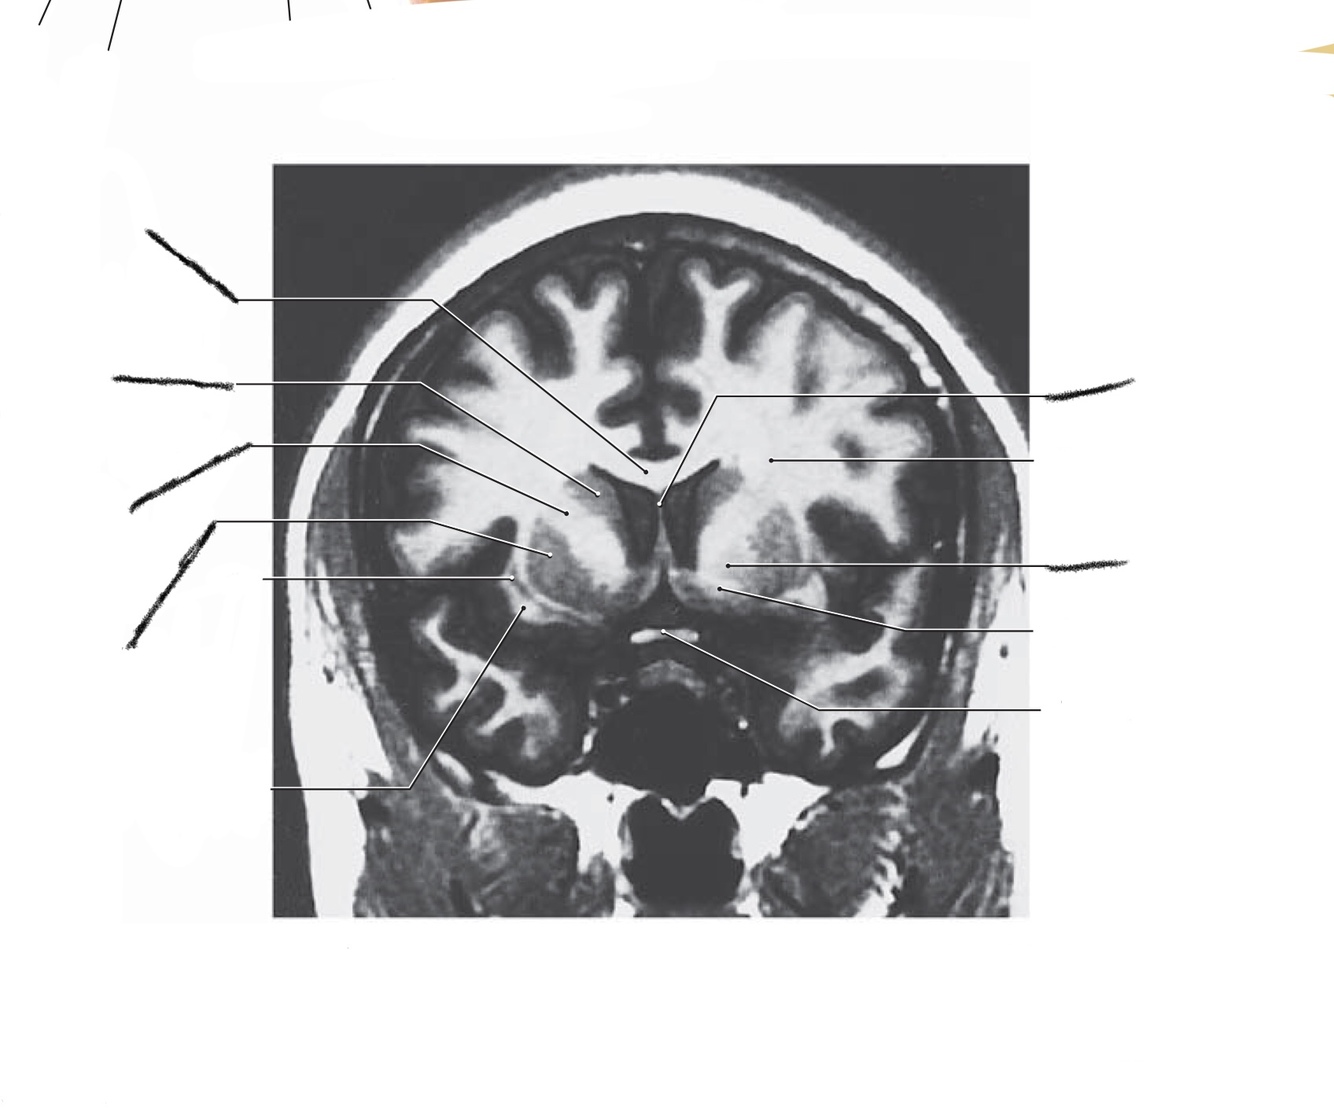

The structure indicated by the red line is?